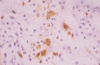

Bilirubin Metabolism

- we have a regular turnover of RBC’s (110 days) and we want to conserve ironand conserve Hb –>happening in spleen

- bilirubin is not solube in water- trafficked using albumin

- conjugated in the hepatocyte –> makes it water soluble (can then float in fluid without carrier)

- conjugated bilrubin will be converted urobilin or stercobilin or can be excreted in the urine

Bilirubin

Bilirubinemia- Hemolysis

- if you have excess break down of RBC’s

- the hepatocytes can only conjugate so much

- the key limiting step though is the EXCRETION INTO THE BILE

- there will be back up into the system, you will start to leak out the conjugated bilirubin which is soluble and you will see it being released in urine

Bilirubinemia - Cholestasis

- Break down of RBCs is normal, the hepatocytes will conjugate the bilirubin

- there is blockage: bilirubin in the blood and in the urine

Bilirubinuria